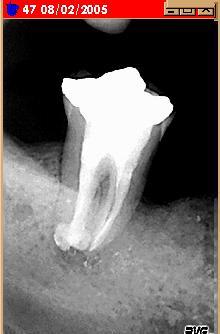

bon, comme je suis un peu tetu et ne me laisse pas faire aussi facilement par une dent à la con : curetage maison par voie "pochstique".

Curetage feu6le - Eugenol

résultat.

j'attend encore un peu pour le bridge.

En bonne voie iaqf7p - Eugenol

et bientot.

Miracle whpizr - Eugenol